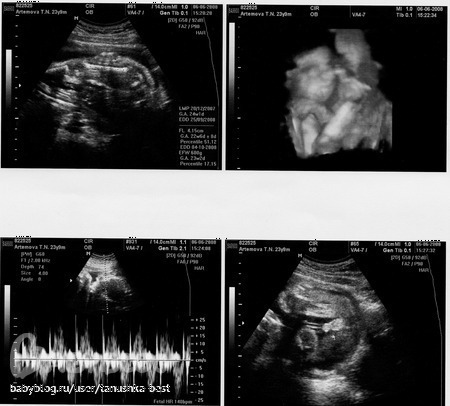

Девочки, Выложила фото нашего УЗИ, нам сказали, что мальчик, но я не могу понять где там что?

Вопросы про УЗИ, обследования и анализы: что, где, как, когда?Если не сложно посмотрите фото нашего УЗИ (сделала пару скриншотов), я чета ниче не понимаю, УЗИстка говорит вот мужской писюн, а я там ниче не вижу, где и что! Аж самой стыдно! Когда там лежала на кушетке, вроде видела, а дома просматривала два раза, ниче не могу понять! А вы кого видите?

Приветик!даже мужа к ноутбуку позвала,он у меня правда травматолог-ортопед,но все же рентген снимки уже множество просмотрел.и про Ваше узи сказал что у Вас мальчик.и зачем Вам кстати делать 3D узи,это долго по времени и мое мнение что все равно вредно чтобы не говорили,иначе ЧСС у плода не учащалось при обследовании,другое дело когда по показаниям.легкой Вам беременности!Вы уже большую половину прошли ))Берегите себя и малыша!

у нас такое же фото было http://www.babyblog.ru/community/post/living/457960 у вас точно мальчик.

Если честно, я на своей как то тоже не особо поняла, что там: мальчик или не мальчик. Но врач сказала, что 100 % мальчик. У девушек так хорошо все можно увидеть, а у нас как и у вас не очень хорошо видно!

Мда.Я,честно говоря, тоже ничегошеньки не понимаю. Вот на нашей фотке в 22 недели трудно не углядеть то самое

я что то даже не поняла где там голова а где ноги))) и уж точно не разглядела писюльку))))

ммммм, обычно на фото с такого ракурса и на таком сроке если мальчик то все мужское достоинство как следует видно. а у вас почему то этого нет

Вот и я что-то не понимаю! Вчера с мужем усиленно разглядывали, пытались углядеть наше достоинство! Не углядели! Просто Хочется уже точно знать, а на следующее узи только в 34 недельки идти! Вот думаю, может на 3D сходить повторно убедиться!

может поможет наша картинка. это с первым сыном делали узи, на правой нижней картинке боком две ножки и писюнок более белый.